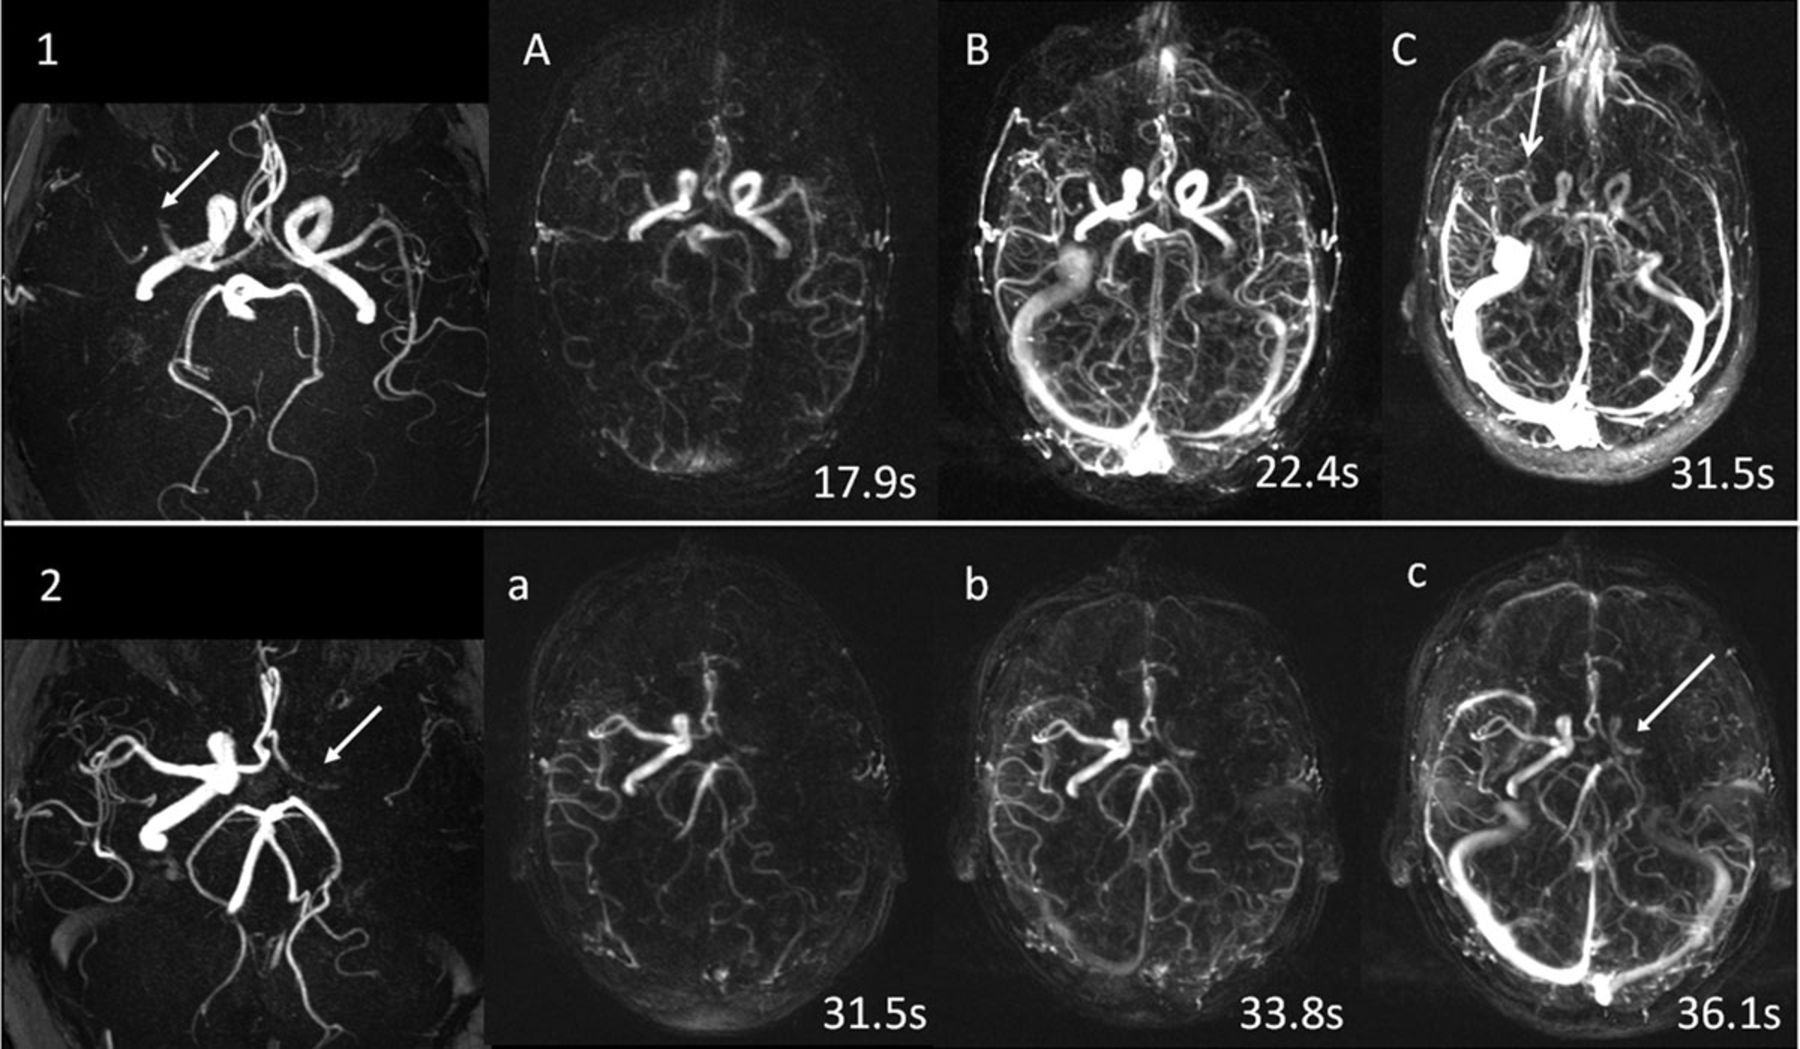

- Состояние сосудов. Оцениваются сосудистые структуры на предмет аневризм, стенозов или других патологий, влияющих на кровообращение.

- Признаки инсульта. В результате могут быть указаны области повреждения, что имеет ключевое значение для выбора дальнейшего лечения.

- Выявление нарушений кровообращения головного мозга, диагностика инсультов и аневризм сосудов.